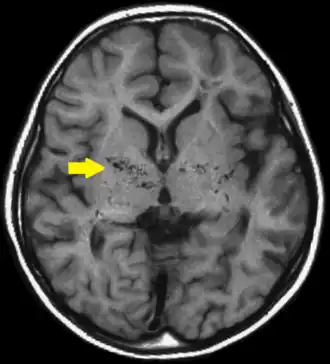

Moyamoya is een ziekte die in de jaren 60 bekend werd in Japan, maar in de rest van de wereld zeldzaam is. Bij Moyamoya treedt een vernauwing van de bloedvaten naar de hersenen op. Omdat de hersenen toch bloed nodig hebben, groeit er een netwerk van haarvaten om de vernauwde bloedvaten heen. Op een scan ziet dit er uit als een rookwolk. In het Japans betekent moyamoya dan ook "rookwolkjes".